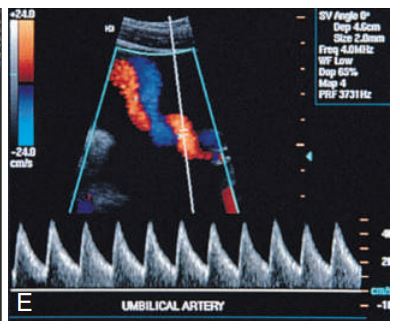

Spectral Doppler shows____ umbilical artery flow in a fetus with a two-vessel cord.

normal